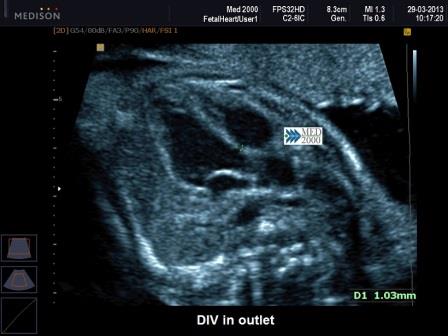

DIV in outlet: appaiono come una discontinuità del tratto setto-aortico e sono evidenziabili in asse lungo di sinistra; se è rispettato l'allineamento tra porzione peri-membranosa del setto interventricolare e parete anteriore dell'aorta, sono dei semplici DIV in autlet della porzione di efflusso. Anche questi difetti sono di tipo evolutivo e quelli molto piccoli possono non essere diagnosticabili nel corso del II trimestre, ma solo nel III trimestre o alla nascita.